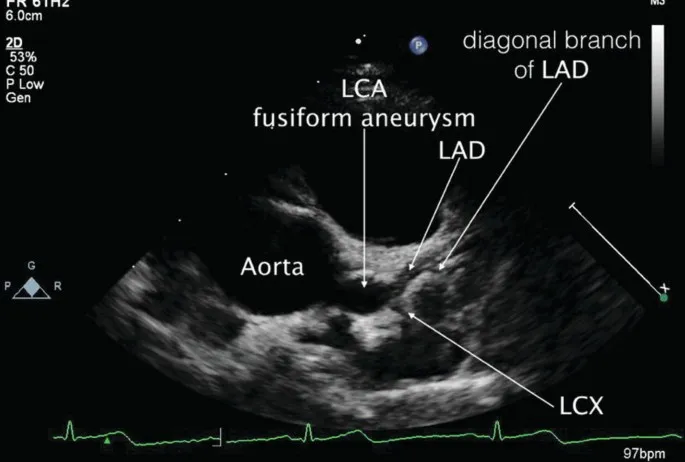

⭐ Atypical/Incomplete KD: Suspect in infants with prolonged unexplained fever, even with <4 criteria. Echocardiography is crucial for diagnosis and assessing coronary artery involvement.

- Baseline echocardiography is mandatory to assess for early cardiac changes.